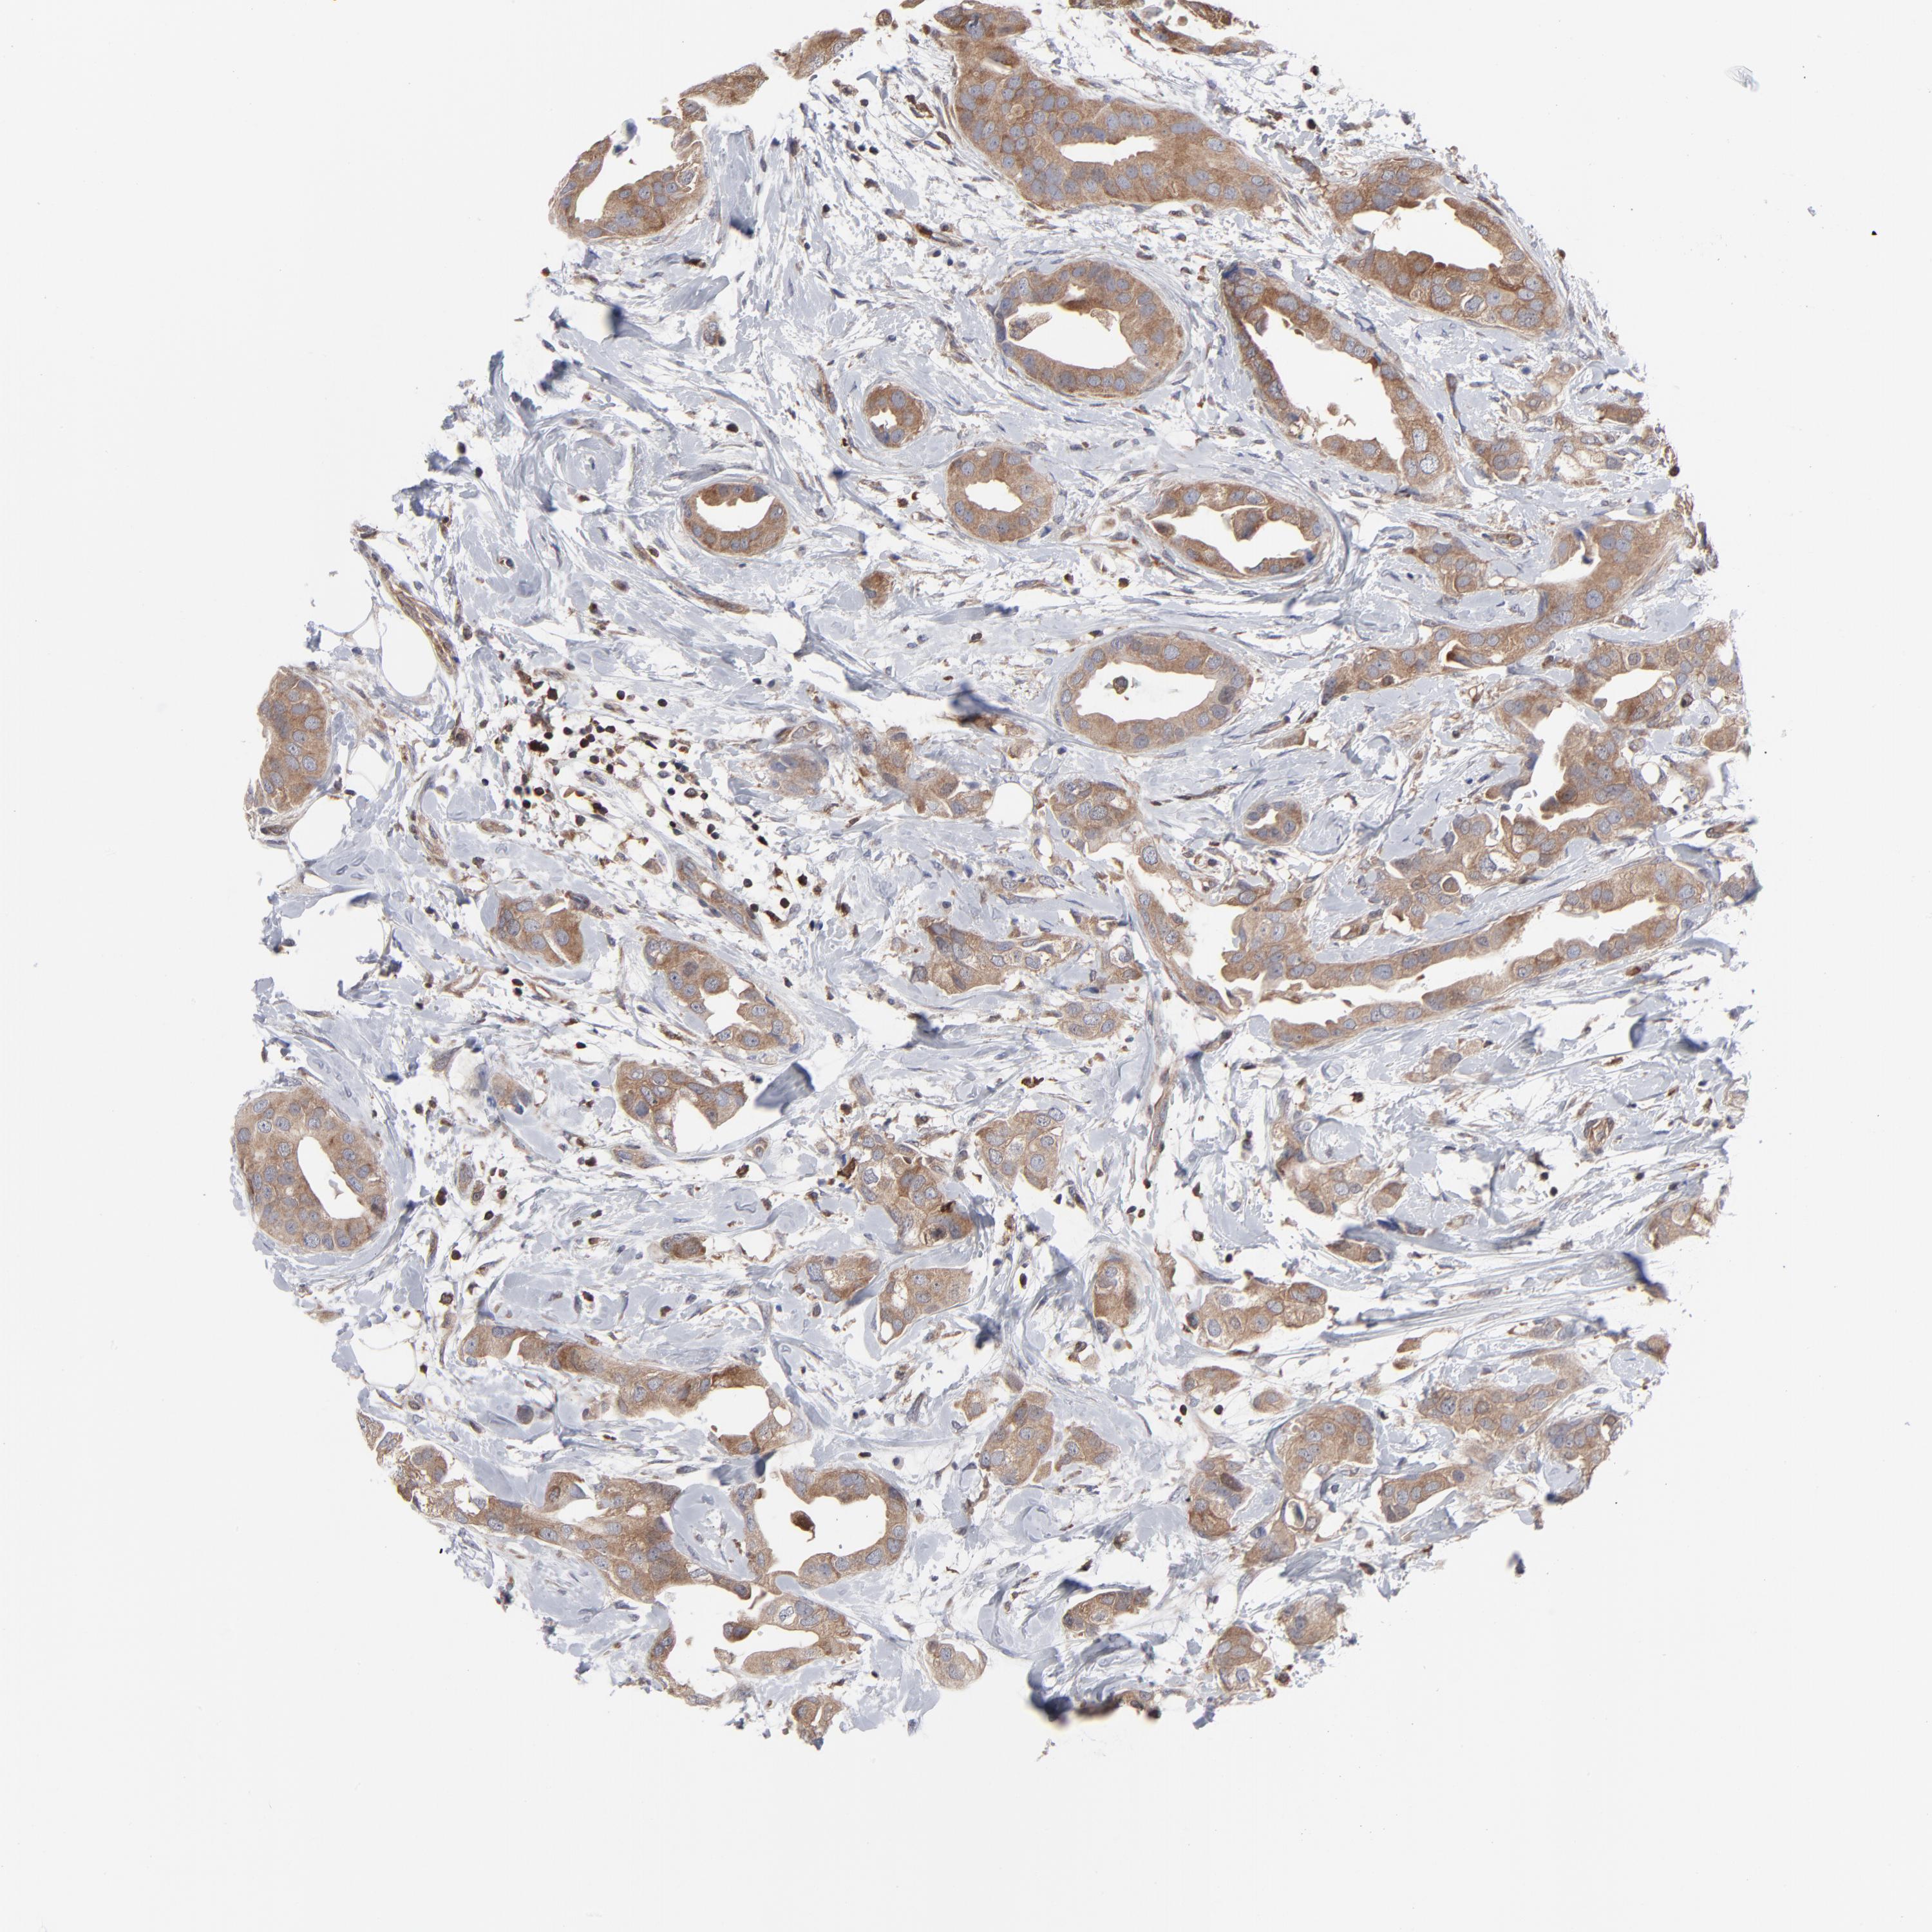

CANCER BREAST CANCER Show tissue menu

BRCA TCGA BRCA VALIDATION PROTEIN EXPRESSION